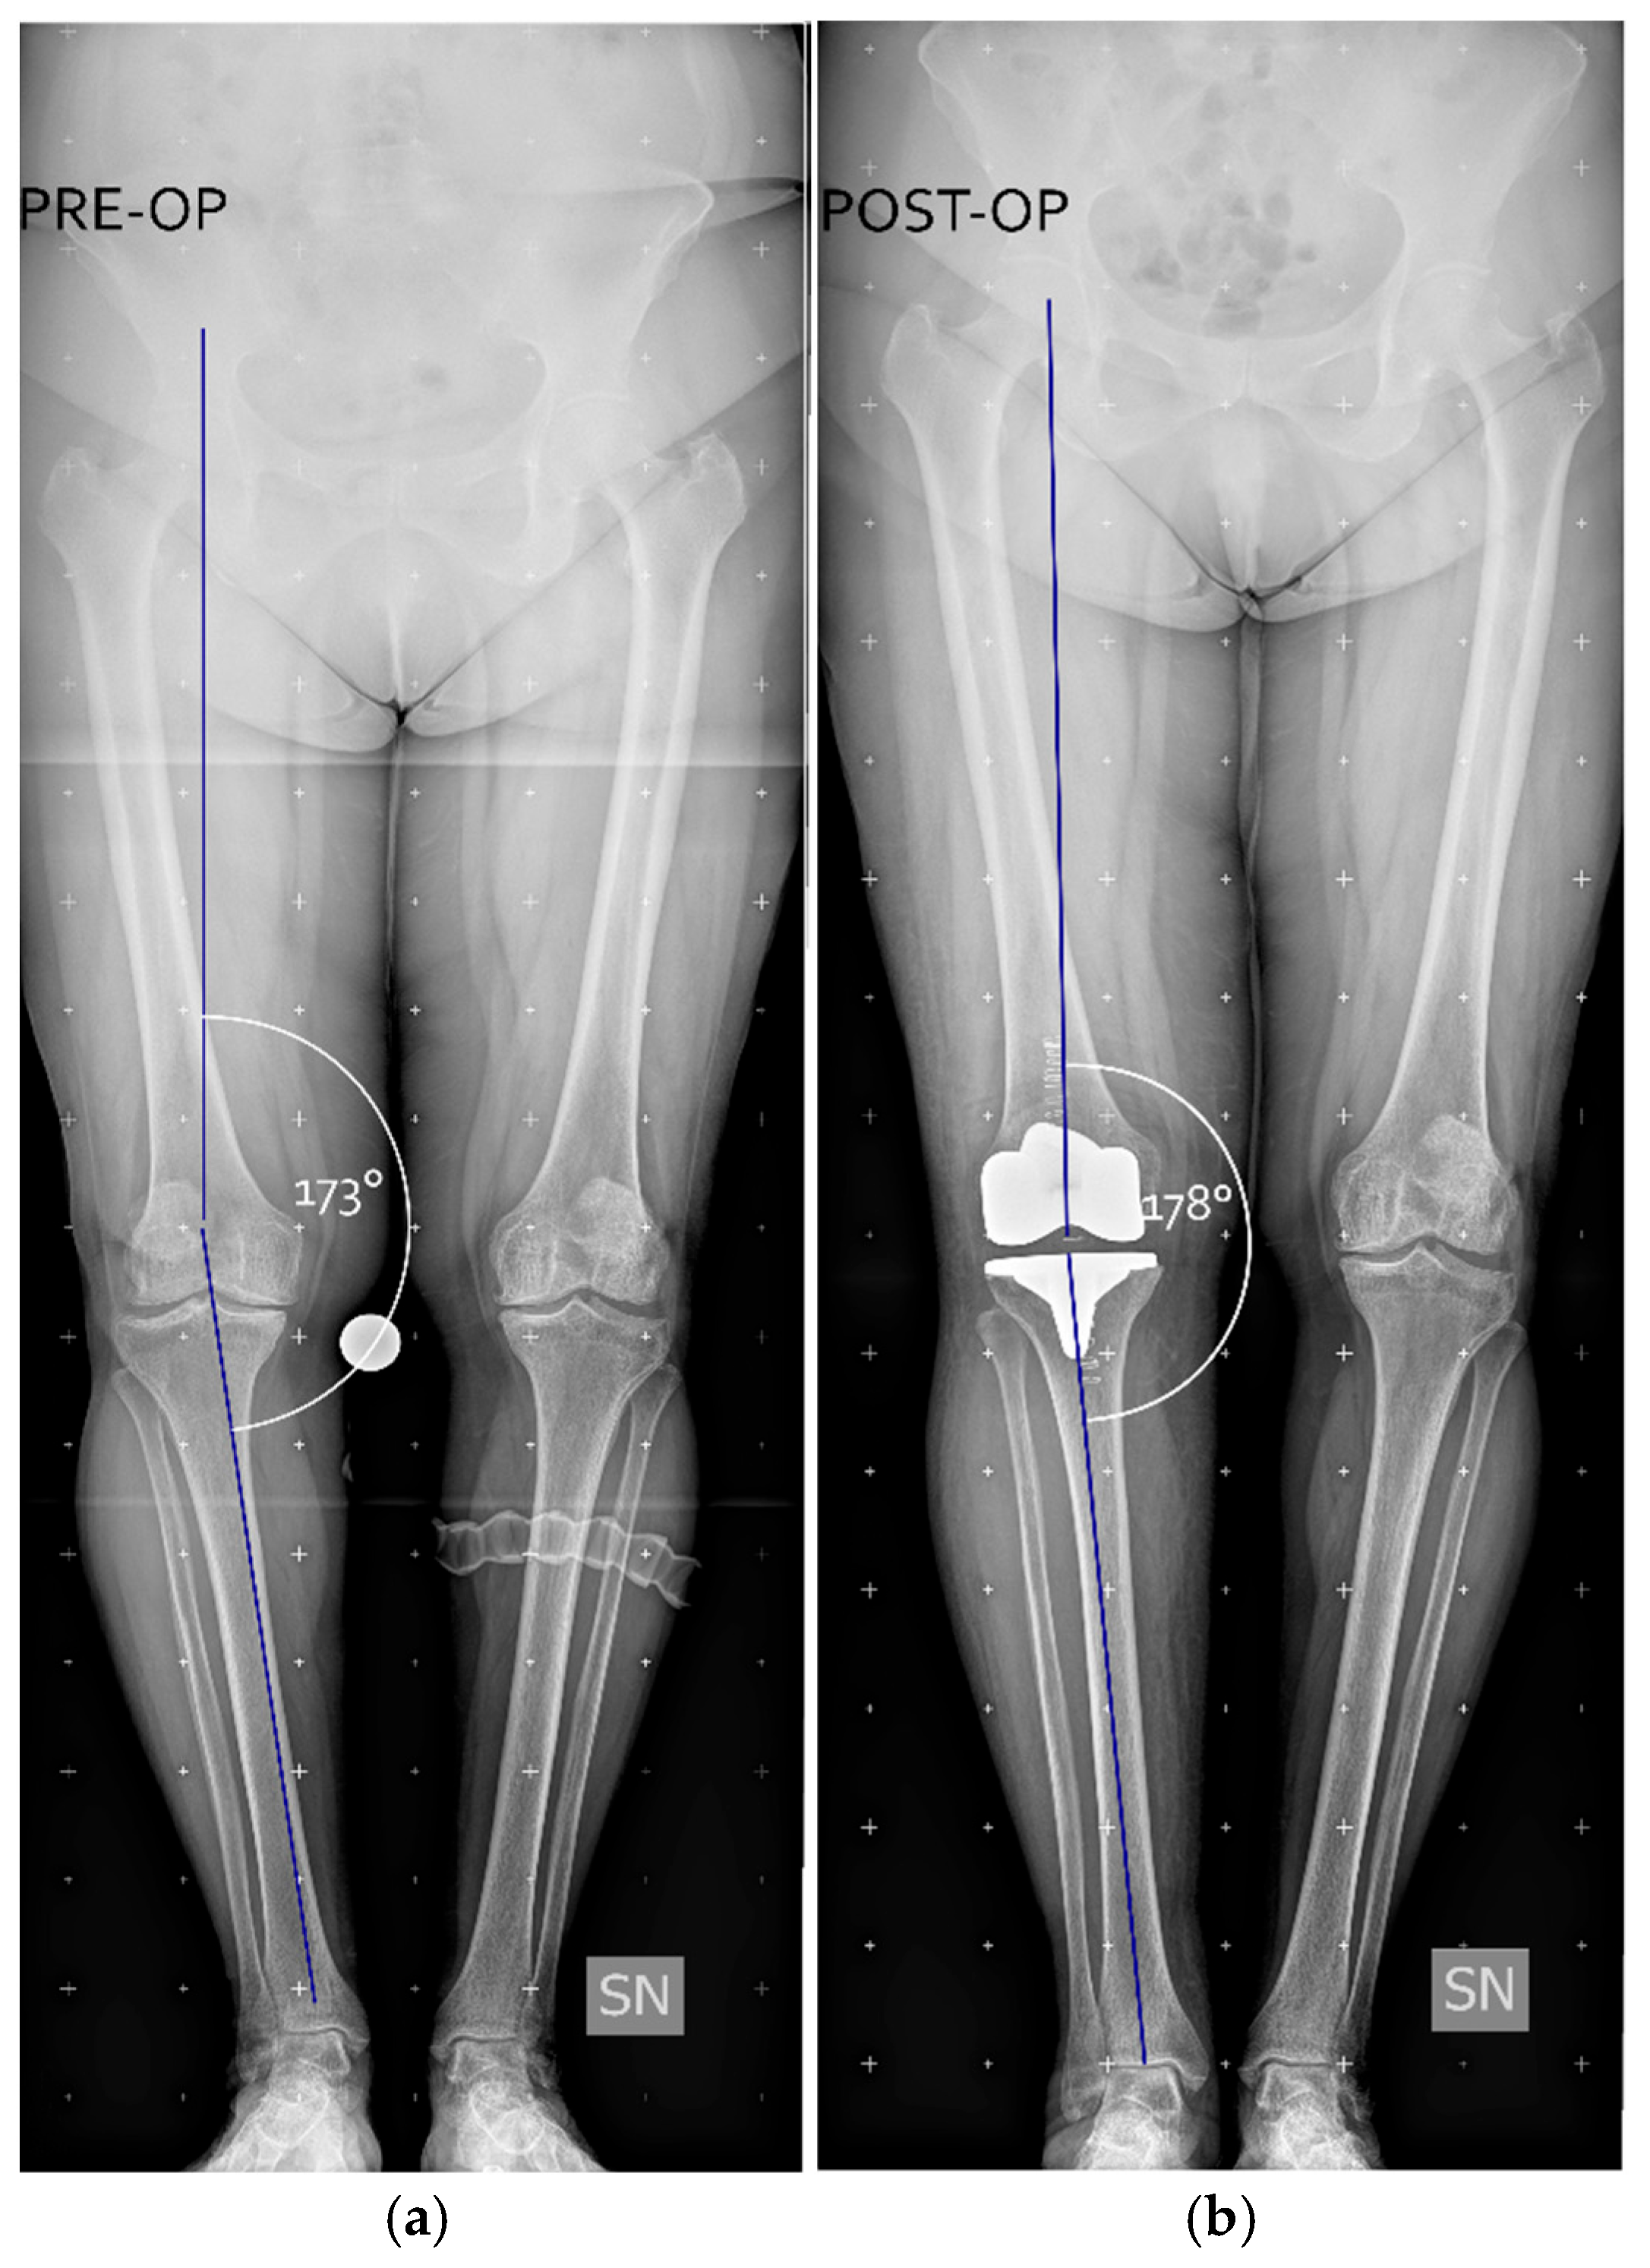

After positioning the prosthesis trials, medial and lateral gaps were reassessed using spacer blocks in both extension and flexion, aiming for symmetrical residual laxity of 1–2 mm in both compartments, with a HKA angle of 176–180°. Figure 3 shows a clinical case where a pre-operative varus aliment of 7° (HKA = 173°) was brought post-operatively to a varus of 2° (HKA = 178°).

Figure 3. Example of a clinical case from the data set. Panel (a) shows a preoperative weight-bearing full leg X-rays with a hip-knee angle (HKA, in white), defined as the angle between the femur and tibia mechanical axes (blue lines), measuring 173°. Panel (b) shows the postoperative correction, with the HKA brought to 178°. Figure created with Inkscape (version 1.4.3, The Inkscape Project, Boston, MA, USA).